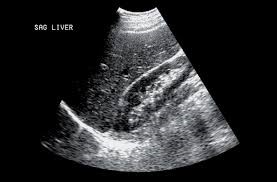

Si cet examen en temps réel est obligatoire chez la femme enceinte au moins trois fois selon l’Organisation mondiale de la santé (OMS), c’est-à-dire à chaque trimestre de la grossesse, il peut également tous nous concerner et peut être prescrit par le médecin pour faciliter le diagnostic de certaines maladies. En effet, elle permet l’étude de multiples organes de l’abdomen, du petit bassin et du cou (thyroïde, ganglions, foie, rate, pancréas, reins, vessie, organes génitaux) mais aussi les vaisseaux (artères et veines), les ligaments et le cœur. Elle recherche des anomalies qui pourraient les atteindre (tumeurs, infections, malformations) et peut parfois guider un prélèvement en profondeur. Les avantages de l’échographie sont bien connus : pas d’irradiation, pas de risque d’allergie, peu de contre-indications. Cet examen est rapidement réalisé, l’image est obtenue en temps réel. Il est indolore et peu couteux. Il peut être réalisé dans n’importe quel endroit via l’échographe portable. Cependant, l’un des inconvénients majeurs de l’échographie est qu’elle est opérateur-dépendant.

- Vésicule biliaire

- Foie en avant de rein droit